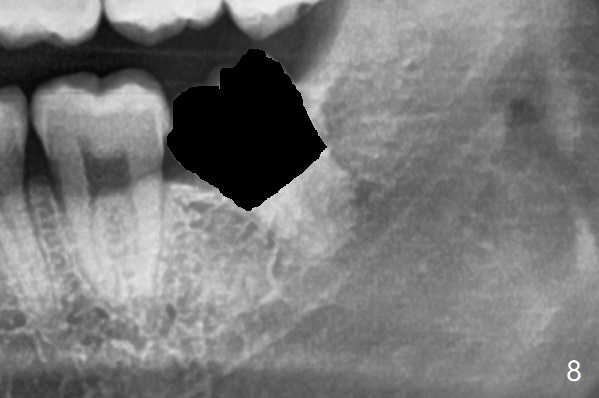

接着除去远中牙冠,并没有松动牙根(图八)。